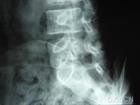

峽部裂多見於下段腰椎。X線平片是診斷脊椎崩裂的首選方法。一般包括站立、負重側位、前後位及左右45°斜位。

正常腰椎X線斜位片上可看到相鄰椎體之間有形似小狗的輪廓(如圖所示),狗脖子處即峽部。如果發生峽部裂,則X線斜位片上表現為狗脖子斷裂。

當然,CT和MRI檢查對於峽部裂有更確定的意義。因為普通X線是二維結構,而這兩者則是三維結構,能進一步反映人體組織的狀態。